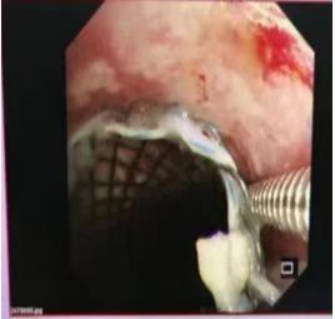

气道肿瘤致气道重度狭窄    气道支架置入后气道打开

支气管镜下取出的支架